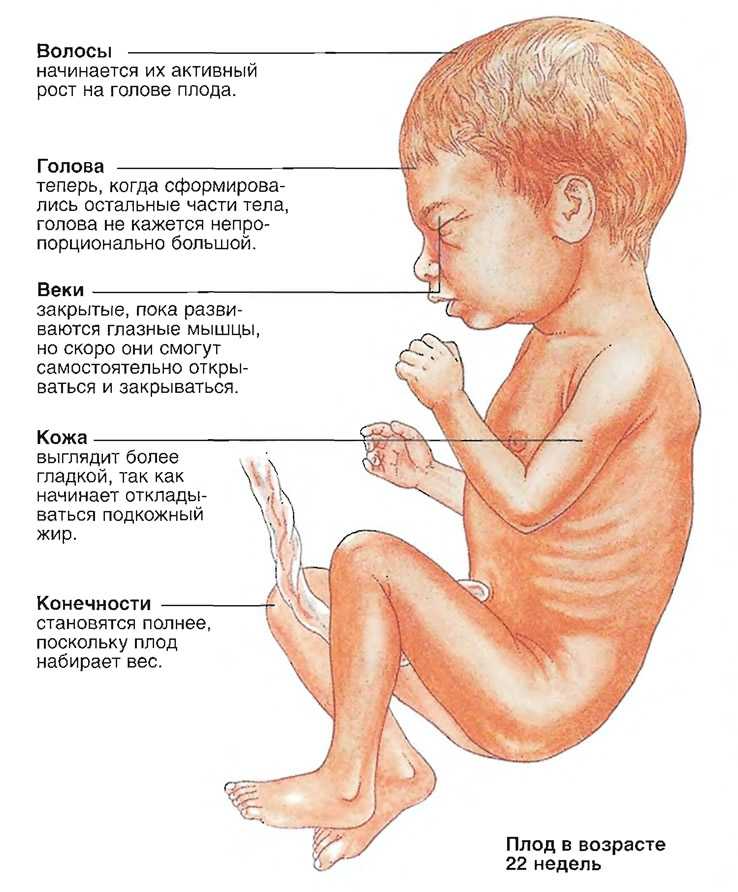

Что происходит с малышом на 22 недели беременности

- В этот период волосы малыша отрастают с особой интенсивностью, но их цвет еще не выражен – пока недостаточно меламина вырабатывает его маленькое тельце.

- Быстро развивается головной мозг. Именно в это время малыш начинает изучать себя и то, где он находится с помощью тактильных ощущений. Именно на 22 неделе беременности ребенок пробует шевелить пальчиками, касаться стенок плаценты и себя. Такое исследование ребенком пространства своего обитания будет усиливаться именно на 22 неделе, так что беременная мама будет хорошо ощущать его прикосновения.

- На стадии 22 недели ребенок в утробе матери останавливает свой рост в высоту. В дальнейшем происходит формирование рефлекторных мышц, они усложняются с каждым днем. Мозговые клетки уже почти сформировались, и мозг весит порядка 95 – 100 г.

- В этот период у ребенка начинается развитие желез внутренней секреции, в частности, потовых желез.

- Продолжают активно формироваться кости – кальций все больше накапливается и откладывается в организме младенца. В связи с этим беременным женщинам прописывают специализированные препараты, содержащие большое количество кальция.

- На 22 неделе беременности развитие позвоночника плода завершает свое формирование. К окончанию второго триместра все позвонки и межпозвоночные диски уже полностью образованы.

- Во время планового УЗИ на 22 неделе беременности на тельце малыша появляются еле заметные волосики, похожие на пух. Они формируют некий вакуум вокруг плода, задерживающий первородную смазку. Кроме этого, смазка защищает ребенка от соприкосновения с водной средой околоплодных вод. Непосредственно перед родами, волосики за ненадобностью исчезают, а предродовая смазка обеспечивает легкий выход малыша из утробы матери.

Какие изменения происходят с плодом на 22 неделе беременности?

На 22 неделе беременности плод продолжает развиваться и весит уже около 450 граммов. Его длина составляет примерно 27 см. Наблюдается активное формирование мозга и нервной системы, а также развитие мышц и костей. Появляются пальчики на ногах и руках, формируются пальцы. Органы слуха продолжают развиваться, а кожа покрывается слоем мягкого волосяного покрова.

Вес ребенка составляет около 680-700 граммов, а рост порядка 22 см. Малыш активно обрастает жирком, идет развитие его костной и мышечной ткани, совершенствуются внутренние органы.

Все части лица уже хорошо сформированы. На глазках есть веки, которые приоткрываются. Выросли реснички и бровки, которые иногда хмурятся. Мимика ребенка пока не сознательна. Если сделать УЗИ в 22 недели, будет видно не только, что происходит с плодом, но и все его структуры лица. Причем, если малыш займет удобное для врача положение, уже можно будет понять, на кого из родителей он больше похож, чей у малыша рот или нос. На память можно будет сделать фото и видеозапись.

У некоторых малышей на голове растет уже много волосиков. Другие почти лысенькие. Но волосы, даже если они есть, пока не имеют цвета, пигмента в них нет. У всех малышей на этом сроке беременности волосы белоснежные.